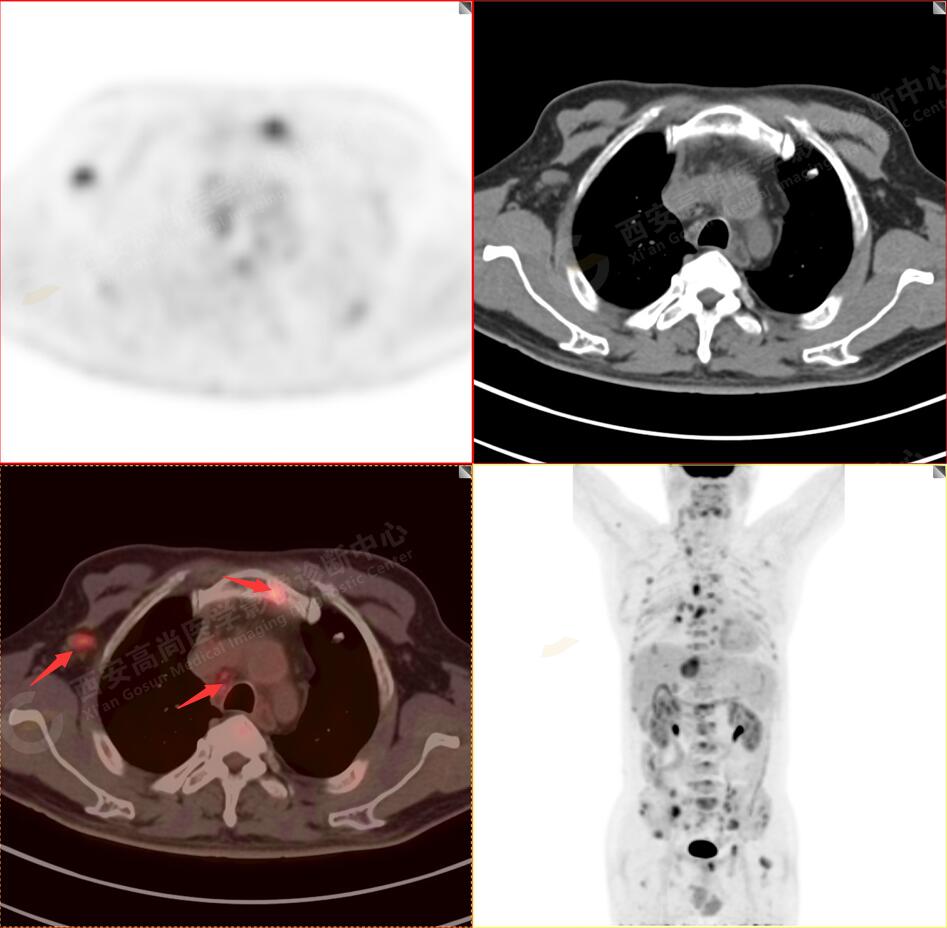

2.以下為全身多發(fā)轉移灶

3.右側頸部(Ⅱ-Ⅴ區(qū))、右側腋窩區(qū)、右側肺門及縱隔(1R、1L、2、4、6、7組)、肝門區(qū)多發(fā)腫大淋巴結,呈不同程度異常增高,均考慮為淋巴結轉移。

4.肝S4、8段團塊狀及結節(jié)狀低密度病變,以S4段病變?yōu)橹什煌潭菷DG代謝異常增高,考慮為肝多發(fā)轉移。

5.右側肱骨上段、左側肩胛骨、右側鎖骨胸骨端、胸骨、雙側多發(fā)肋骨、脊柱多發(fā)椎體及附件、雙側髂骨、雙側髖臼、雙側恥骨、雙側肱骨上段多發(fā)成骨性病變,呈不同程度FDG代謝異常增高,考慮為多發(fā)骨轉移瘤。